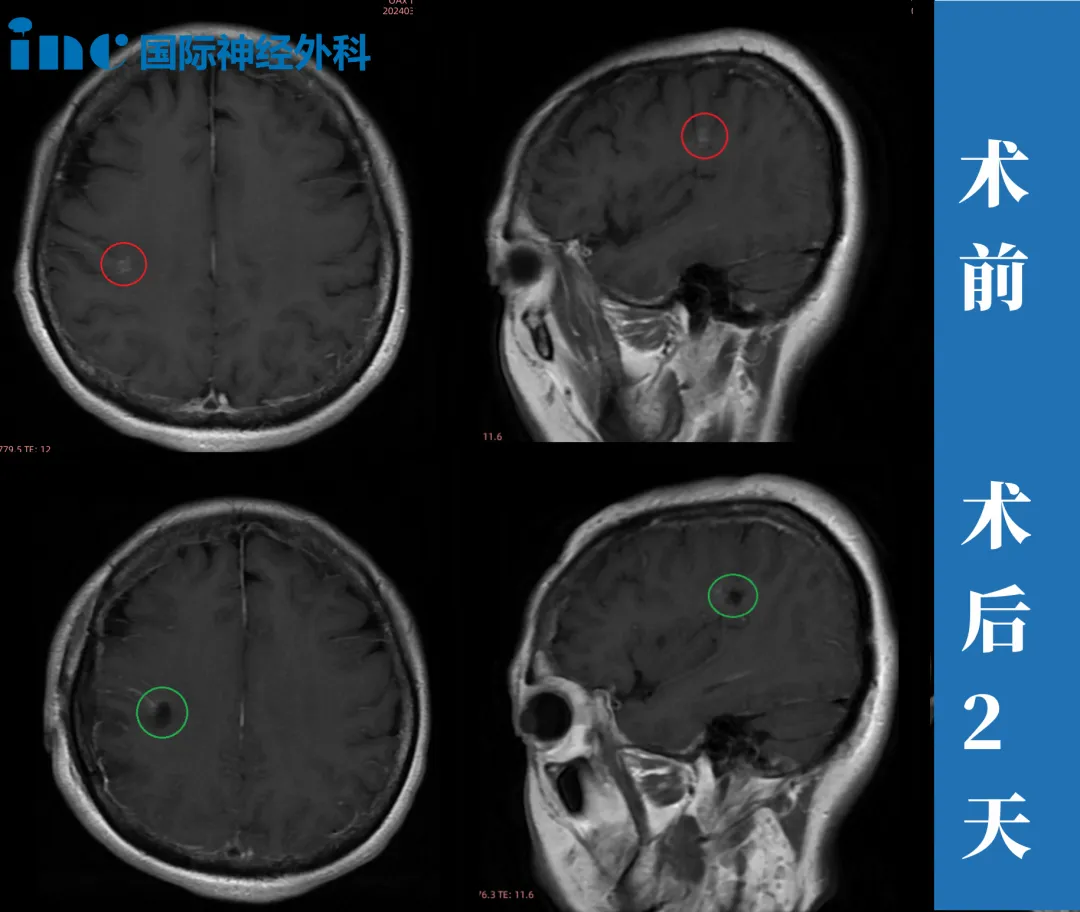

47岁女性—功能区海绵状血管瘤

“找了一些脑外科的专家,他们都看了片子说,你这个位置太深,而且现在没有症状,随访就可以了,不建议手术,做手术毕竟风险太大,但是有可能以后会引发癫痫。

(巴教授手术后)麻醉清醒后,突然说了一句英文——我自己也笑死了,我这个大概是大脑会潜意识的一种反应吧,我觉得就是想表达我对他的感谢。而且我在ICU没什么大问题,因为我当天就能讲话了,思路也很清晰,手脚也都能动。”

▼术后4天,邓女士已经下床吃饭,手术切口也恢复的好。